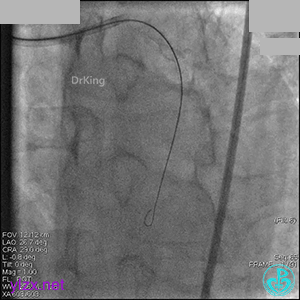

1周后再次上台,右冠脉3级血流,3段局限性严重狭窄,内膜模糊,应该是上次操作夹层遗留下的血肿。

先处理前降支开口严重狭窄并顺利植入前降支到左主干支架。